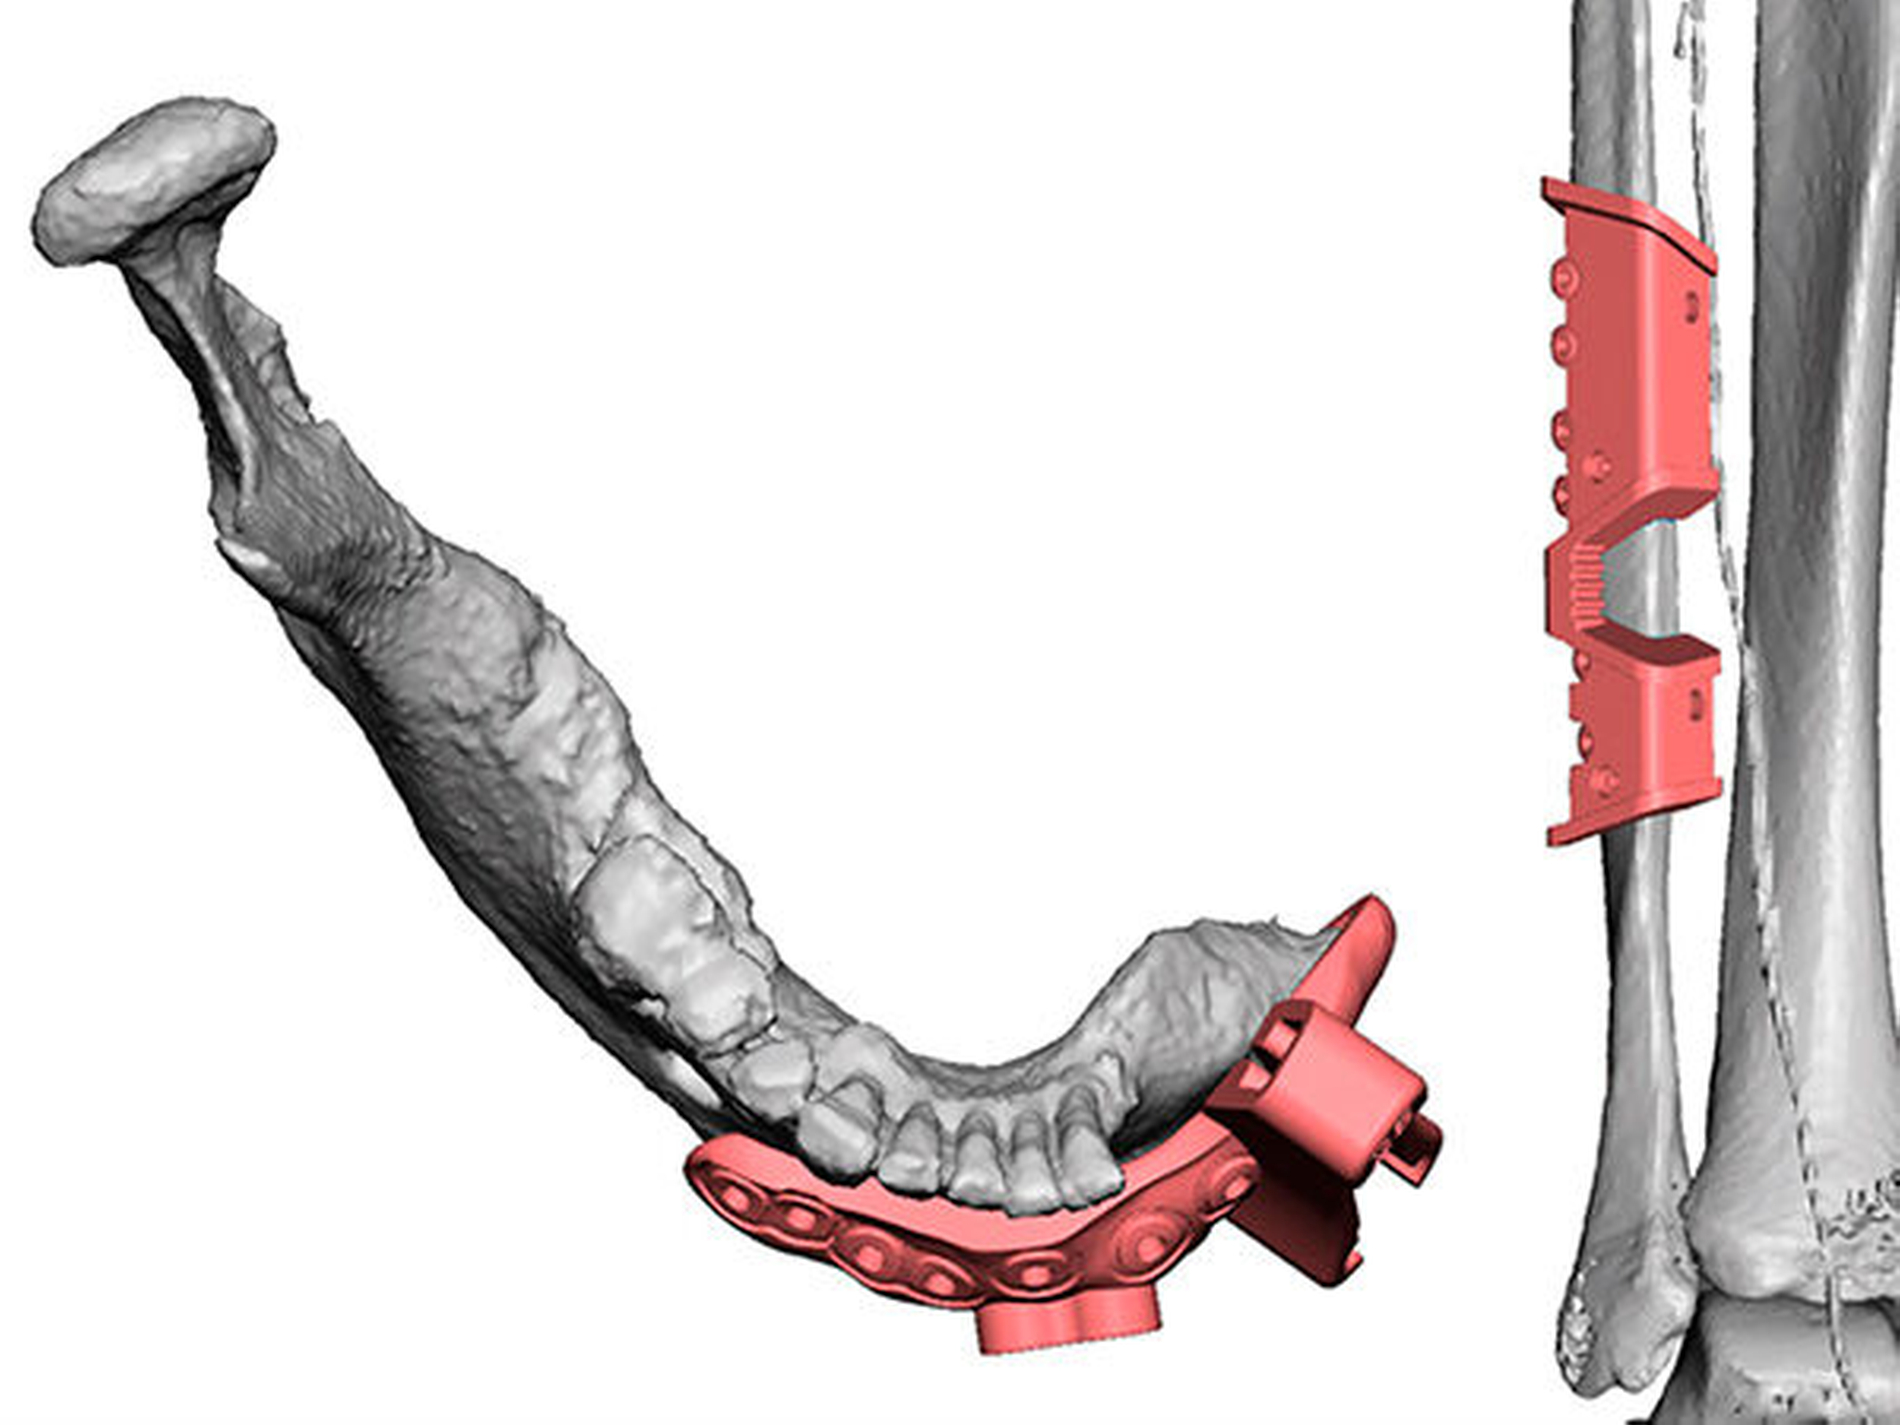

In Abbildung 8 sind die notwendigen Resektions- und Bohrschablonen dargestellt, die intraoperativ die Schnittgrenzen und Bohrlöcher festlegen.

Im Intervall begann die Planung der notwendigen dentalen Implantation. Wir haben uns für die Verwendung von Implantaten der Firma Straumann (Institut Straumann AG, Basel, Schweiz) entschieden. Dem Behandler wird ein großes Portfolio an unterschiedlichen Implantat-Designs und entsprechenden prothetischen Aufbauten zur Verfügung gestellt, das bei komplexen Fällen notwendig werden kann. Im ersten Schritt stellte das zahntechnische Labor Schuldes (Dental Labor Schuldes GmbH, Eisenach) eine Scanschablone her, mit der die CT durchgeführt wurde (Abbildung 11).

Nachfolgend konnte im Backward-Planning mit der Planungssoftware coDiagnostiX (Dental Wings GmbH, Chemnitz) die möglichst optimale Position der Implantate in Bezug auf die transplantierte Fibula und Gegenkiefer festgelegt werden (Abbildung 12). Es erfolgte die Umwandlung in eine full guided-Bohrschablone für das Straumann Guided Surgery System.